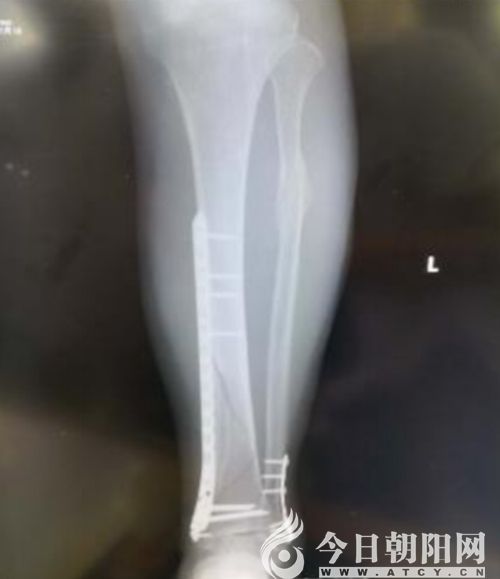

術(shù)后X線

隨著社會(huì)的進(jìn)步與發(fā)展,人們對(duì)外傷骨折的治療要求越來(lái)越高,朝陽(yáng)市中心醫(yī)院骨外三科結(jié)合大量臨床經(jīng)驗(yàn),積極探索引進(jìn)了微創(chuàng)經(jīng)皮鋼板內(nèi)固定(MIPPO)技術(shù)。運(yùn)用“內(nèi)支架”概念進(jìn)行骨折固定,用鋼板對(duì)骨折行橋接固定,利用肌腱復(fù)位作用及間接復(fù)位技術(shù)進(jìn)行骨折復(fù)位。

朝陽(yáng)市中心醫(yī)院骨三科主任胡剛介紹:“骨折治療的目的是盡早使肢體功能恢復(fù)到受傷前的水平以及減少并發(fā)癥的發(fā)生。與傳統(tǒng)開放式骨折治療方法相比,MIPPO技術(shù)遠(yuǎn)離骨折部位進(jìn)行復(fù)位,為骨折愈合、軟組織修復(fù)提供良好的生物學(xué)環(huán)境,能最大程度地保護(hù)骨折處血供,促進(jìn)骨折愈合,減少感染和再骨折的危險(xiǎn)性,維持骨折穩(wěn)定性。MIPPO技術(shù)在我科的成功應(yīng)用,充分證明了我院骨科人攻堅(jiān)克難的能力與決心,我們將不斷探求微創(chuàng)新技術(shù),更好地造福朝陽(yáng)百姓。”